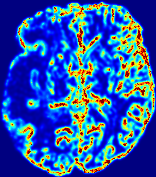

Slice #1Slice #2Slice #3Slice #4Slice #5Slice #6Dgtsuperscript𝐷gtD^{\text{gt}}Refer to captionRefer to captionRefer to captionRefer to captionRefer to captionRefer to captionDestsuperscript𝐷estD^{\text{est}}Refer to captionRefer to captionRefer to captionRefer to captionRefer to captionRefer to captionRefer to caption0.300.300.300.240.240.240.180.180.180.120.120.120.060.060.060.000.000.00(mm2/s)𝑚superscript𝑚2𝑠(mm^{2}/s)𝐕est𝟐subscriptnormsuperscript𝐕est2\|\bf{V}^{\text{est}}\|_{2}Refer to captionRefer to captionRefer to captionRefer to captionRefer to captionRefer to captionRefer to caption0.00300.00300.00300.00240.00240.00240.00180.00180.00180.00120.00120.00120.00060.00060.00060.00000.00000.0000(mm/s)𝑚𝑚𝑠(mm/s)

Figure 15: PIANO identifiability testing: diffusion imaging via advection-diffusion. Top row shows Dgtsuperscript𝐷gtD^{\text{gt}} used for simulating ground truth pure diffusion. Rows below show the estimated Destsuperscript𝐷estD^{\text{est}} and 𝐕est2subscriptnormsuperscript𝐕est2\|{\bf{V}}^{\text{est}}\|_{2} on corresponding slices. Note that the plotted value scale for 𝐕est2subscriptnormsuperscript𝐕est2\|{\bf{V}}^{\text{est}}\|_{2} is 0.01 of that for Dgtsuperscript𝐷gtD^{\text{gt}} and Destsuperscript𝐷estD^{\text{est}}.

Similarly, we test the behavior of PIANO when estimating both advection and diffusion from a pure diffusion-driven process. The goal is to determine if PIANO is able to recognize that there is only diffusion governing the given concentration time-series. We use the same ‘Diffusion Imaging’ data simulation of Sec. 4.2.1 as the concentration dataset, PIANO estimates both velocity 𝐕estsuperscript𝐕est{\bf{V}}^{\text{est}} and diffusivity Destsuperscript𝐷estD^{\text{est}}. Estimation results in Fig. 15 confirm PIANO’s identifiability again: the estimated 𝐕est2subscriptnormsuperscript𝐕est2\|{\bf{V}}^{\text{est}}\|_{2} is almost invisible compared to Destsuperscript𝐷estD^{\text{est}}, even plotted with a 1%percent11\% value range compared to that for Destsuperscript𝐷estD^{\text{est}}. On the other hand, Destsuperscript𝐷estD^{\text{est}} achieves comparable estimation performance as ‘Diffusion Imaging via Diffusion’ in which PIANO predicts Destsuperscript𝐷estD^{\text{est}} alone (shown in Fig. 13).